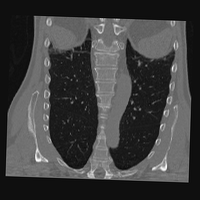

Exp. 3: Adult thorax data: To show the versatility of our approach we also apply it to adult thorax scans. For this experiment no organ specific training is performed but the whole volume is used. We evaluate reconstruction performance similar to Exp. 1 and Ti^^subscript𝑇𝑖\hat{T_{i}} prediction performance when ΩΩ\Omega is projected on an external plane, comparable to X-Ray examination using C-Arms. The latter provides insights about our method’s performance when applied to interventional settings in contrast to motion compensation problems. 60 healthy adult thorax scans were randomly selected, 51 scans used for ΩtrainsubscriptΩ𝑡𝑟𝑎𝑖𝑛\Omega_{train} and nine scans used for ΩvalidationsubscriptΩ𝑣𝑎𝑙𝑖𝑑𝑎𝑡𝑖𝑜𝑛\Omega_{validation}. Each scan is intensity normalised and resampled in a volume of 200×200×200200200200200\times 200\times 200 with spacing 1mm×1mm×1mm1𝑚𝑚1𝑚𝑚1𝑚𝑚1mm\times 1mm\times 1mm. Using the Fibonacci sampling method, 25 sampling plane of size 200×200200200200\times 200, evenly spaced between -50 and +50, were rotated over 500 normals. Training took approximately 20 hours for 60 epochs. Fig. 4c shows an example reconstruction result gaining 28dB PSNR with additional SVR. Ti^^subscript𝑇𝑖\hat{T_{i}} prediction takes approx. 20 ms/slice for this data.

Figure 4: (a): Comparison of a single slice from raw low-dose thorax CT data; (b): reconstruction based on SVRNet Ti^^subscript𝑇𝑖\hat{T_{i}} regression; (c): SVR initialized with SVRNet transformations after four iterations of SVR; (d): PSNR of (b) and (c) compared to (a). (e): shows a projection of an unseen pathological test CT volume as DRR and (e) shows a DRR at the location predicted by our method when presented with the image data in (e).

We use Siddon-Jacobs ray tracing [15] to generate Digitally Reconstructed Radiographs (DRRs) from the above described data. For training, we equally sample DRRs on equidistant half-spheres around 51 CT volumes at distances of 80cm, 60cm, and 40cm, between 90superscript90-90^{\circ} and 90superscript9090^{\circ} around all three co-ordinate axes. For validation, we generate 1000 DRRs with random rotation parameters within the bounds of the training data at 60cm distance from the volumetric iso-centre. We trained on healthy volunteer data and tested on nine healthy and ten randomly selected pathological volumes (eight lung cancer and two spinal pathologies). Our approach is able to predict DRR transformations relative to the trained reference co-ordinate system with an average translation error of 106mm and 5.6superscript5.65.6^{\circ} plane rotation for healthy patients, and 130mm and 7.0superscript7.07.0^{\circ} average error for pathological patients. An example is shown in Fig. 4e,f. Note that these values are good enough to robustly initialize intensity-based registration refinement. SVRNet prediction can be improved by generating a denser training data set, in particular, in more equidistant half-spheres.